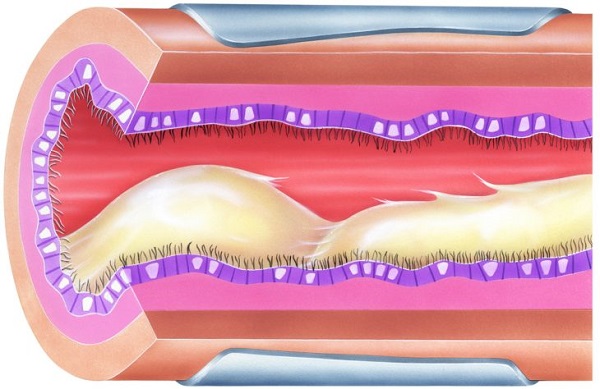

Бронхи человека исполняют важную функцию в процессах газообмена. Они очищают и согревают воздух, проводят его к легочной ткани, продуцируют слизь и защищают легкие от проникновения в них микроорганизмов. Очень часто подвергается воспалению именно бронхиальное дерево. Таким образом развивается обструктивный бронхит.

Обструктивный бронхит – это болезнь, которая характеризируется воспалением бронхов с их обструкцией. Данное заболевание осложняется отеком дыхательных путей и падением вентиляционной способности легочной ткани. Чаще всего обструктивный бронхит возникает у детей 3-10 лет, так как их дыхательная система не до конца сформировалась. Также бронхит может развиваться у взрослых и пожилых людей.

Главные симптомы заболевания – это одышка и сильный кашель. Кашель чаще всего возникает ночью. Он продолжается долго и не приносит облегчения. Кашель сопровождается выделением небольшого количества вязкой, липкой мокроты. Именно она мешает человеку дышать.

Одышка возникает из-за накопления в бронхах густой мокроты, которая не пропускает воздух и утрудняет дыхание. Во время отдышки появляются громкие, свистящие хрипы.